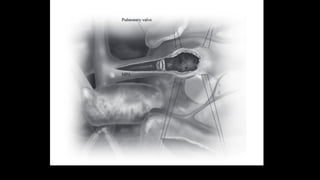

Exposure of ventricular septal defect

and right ventricular outflow tract

through tricuspid valve. B:

Infundibular resection is complete

and pulmonic valve can be seen.